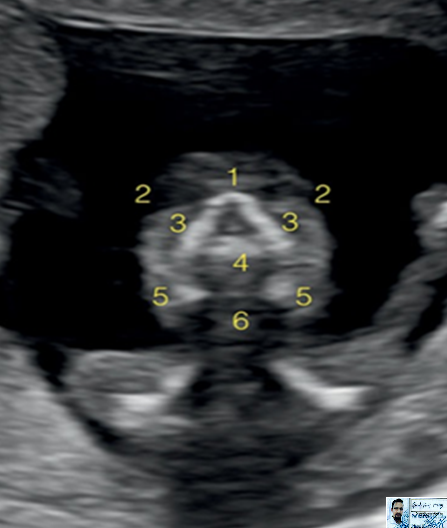

1- Thalami

2- Developing cerebellum

3- Fourth ventricle

4- Choroid plexus of fourth ventricle

5- Cisterna magna